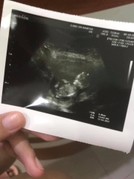

อยากเห็นรูปอัลตราซาวด์ตอน12วีค

ซาวด์ครั้งแรกตอน6วีค ตอนนี้12วีคแล้วอยากรู้ว่าขนาดประมาณเท่าไหน หมอนัดอาทิตย์หน้า #ท้องแรก

บ้านนี้ได้ 6 ซม. ค่ะ